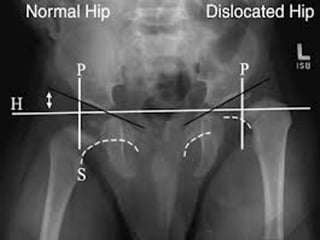

• Congenital dislocation is more common in hip

than in any other joint of the body.the head

of femur slips upwards on to the gluteal

surface of the ilium because the upper

margin of the acetabulum is developmentally

deficient .this causes lurching gait &

trendelenburg +ve.

• SHENTONS LINE in an x-ray,is a continous

curve formed by upper border of obturator

foramen 7 the lower border of the neck of the

femur.In # neck femur ,line becomes

abnormal.